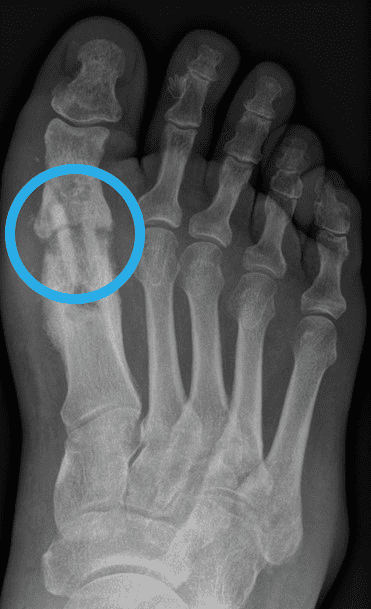

Was ist eine Pseudarthrose? Wenn es 6 Monate nach einem Bruch nicht zur Heilung des Knochens gekommen ist, spricht man laut Definition von einer Pseudarthrose. Zur Heilung werden bei Operationen in der Regel Schrauben aus menschlichem Knochen verwendet. Das Wort Pseudarthrose stammt aus dem Griechischen, wobei „pseudos“ falsch bedeutet und „arthros“ Gelenk. Eine Pseudarthrose ist auch unter den Namen Pseudogelenk oder Scheingelenk bekannt. Pseudarthrosen treten immer nach einem Knochenbruch oder einer Knochenoperation auf, wenn der Knochen nicht richtig verheilt, die Knochenstücke nicht zusammenwachsen. Solange der Knochen nicht vollständig geheilt ist, kann er auch nicht richtig belastet werden. „Auslöser einer nicht heilenden Fraktur ist meist eine zu frühe Belastung, aber auch Entzündungen und Infektionen können den Knochenheilungsprozess einschränken. Der Knochen wächst nach einem Bruch nicht zusammen und in der Folge entsteht die Pseudarthrose.“ So der Experte aus Linz, Dr. Klaus Pastl. Pseudarthrosen können an jedem Knochen, der nicht verheilt, auftreten, egal ob es sich um eine nicht heilende Mittelfuß- Operation, eine fehlgeschlagene Hallux rigidus Operation oder eine nicht heilende Operation nach einem Kahnbeinbruch handelt. Tritt eine Pseudarthrose auf, muss diese behandelt werden.

Symptome einer Pseudarthrose

Ein eindeutiges Anzeichen einer Pseudarthrose ist, wenn die Knochenbruchenden innerhalb von 4 – 6 Monaten nicht stabil zusammengewachsen sind. Weitere typische Symptome einer Pseudarthrose sind Rötungen, Schmerzen und Schwellungen über dem nicht geheilten Knochenbereich. „Da durch die Pseudarthrose die Stabilität des Knochens stark beeinträchtig ist, treten häufig Fehlstellungen, Bewegungseinschränkungen, Gelenksprobleme aber auch Muskelschwund in der betroffenen Region auf.“, erklärt Dr. Klaus Pastl, Orthopäde aus Linz. Bei den meisten Betroffenen treten Schmerzen anfangs nur bei Bewegung und Belastung auf. Schreitet die Pseudarthrose fort, treten die Schmerzen und Symptome aber auch in der Ruhephase auf. Tritt eine Pseudarthrose nach einer Implantation von Metallschrauben oder Metallplatten auf, ist ein zu spätes Reagieren besonders gefährlich. Heilt der Knochen nicht rechtzeitig, lastet das gesamte Gewicht auf den Metallplatten und Metallschrauben. Diese können durch die Belastung brechen. „Gebrochene Metallteile im Körper können äußerst schmerzhaft für Patienten sein. Auch für den Chirurgen sind diese Operationen äußerst unangenehm und schwierig. „Operationen sind mühsam und komplex. Oft muss viel Knochen zerstört und die umgebenden Weichteile verletzt werden, um die gebrochenen Metallteile aus dem Knochen des Patienten zu bergen. Manchmal können nicht alle Metallteile entfernt werden und müssen dann im Knochen verbleiben. Das ist frustrierend, für Patienten und Chirurgen.“

Wie wird eine Pseudarthrose diagnostiziert?

Die Diagnose einer Pseudarthrose wird über Röntgenbilder gestellt. Bei unklaren Röntgenbefunden kann auch eine Computertomographie (CT) oder Kernspintomographie (MRT) sinnvoll sein.